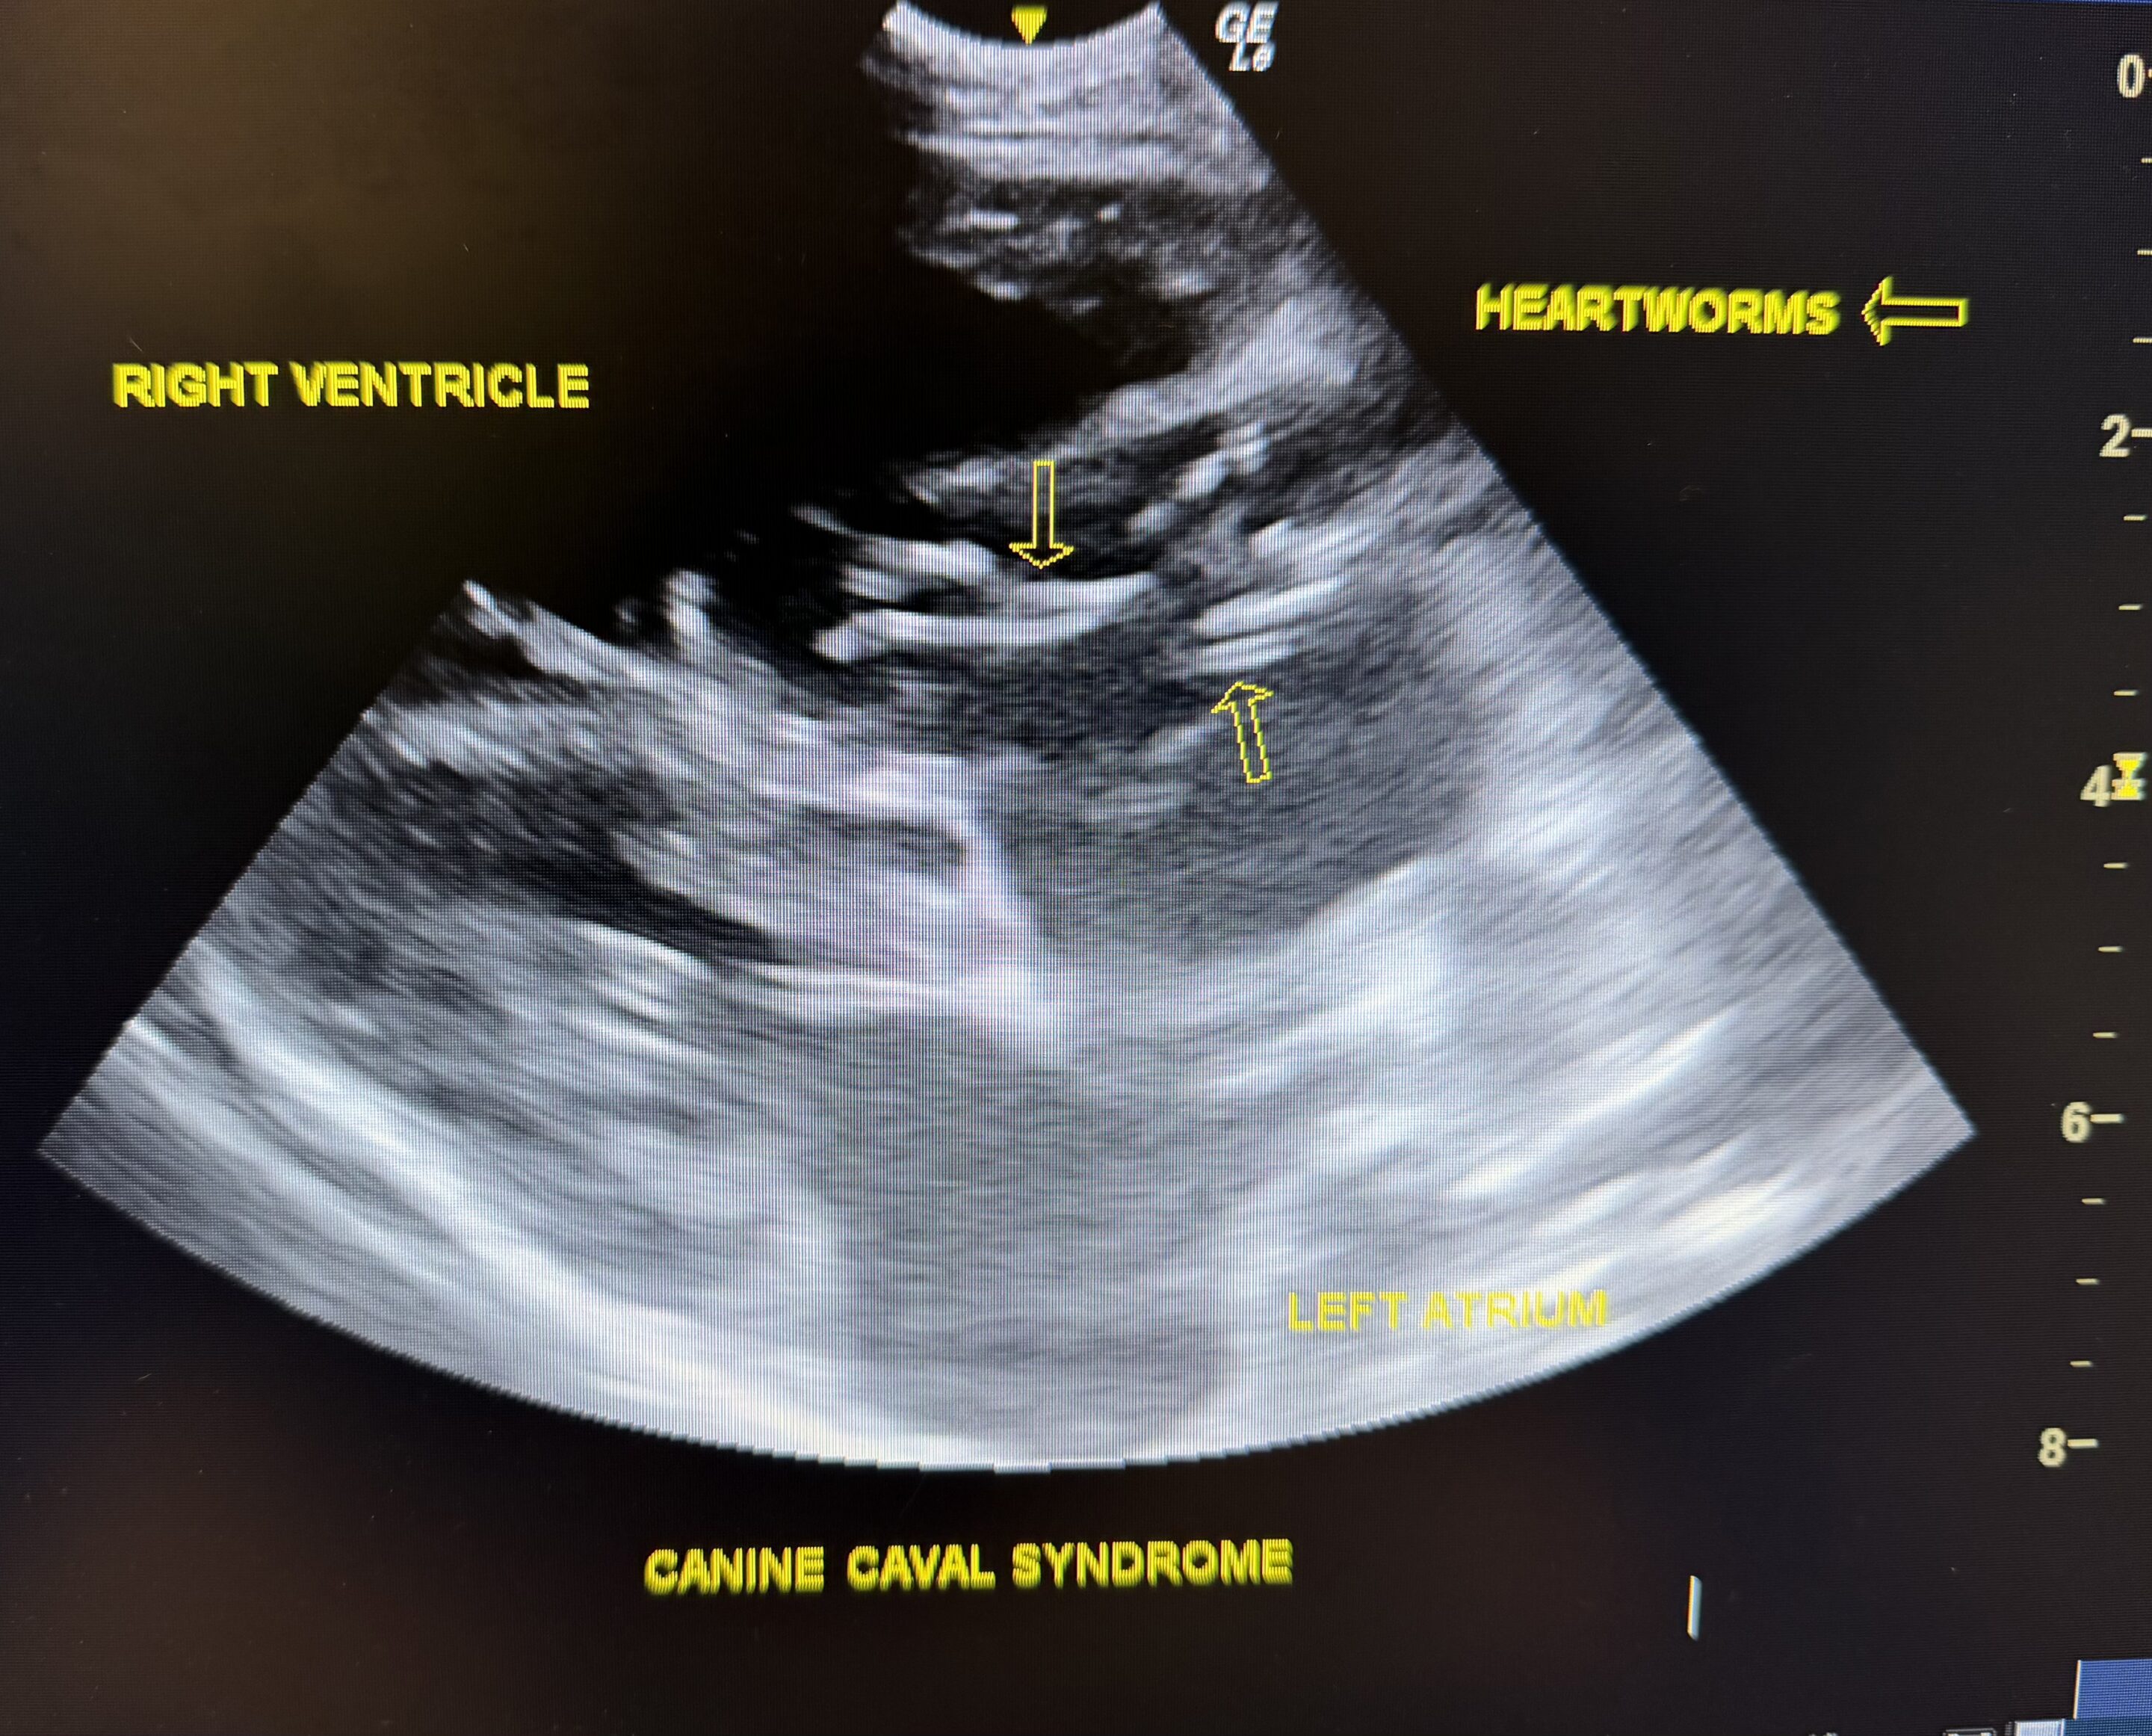

A pet ultrasound is a diagnostic imaging technique that uses sound waves to create real-time images of your pet’s internal organs. This painless procedure allows veterinarians to examine areas such as the heart, liver, kidneys, bladder, and abdominal organs without the need for surgery or invasive tests. It is often used to assess soft tissue structures and monitor ongoing conditions.

- Versatile Diagnostics: Whether used for identifying tumors, fluid buildup, or organ abnormalities, ultrasound is an adaptable tool for a wide range of health concerns.

- Heart or Liver Disease Monitoring